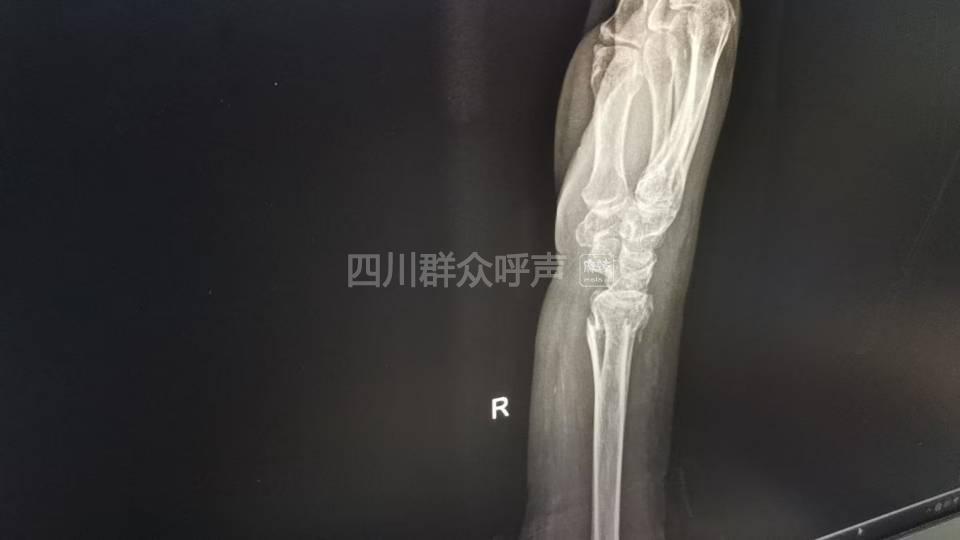

[投诉] 家属因道路施工不规范导致受伤需及时帮助

有人对接属实,伤者从入院至今无相关人员去医院看望,对我家属提出的诉求未给予明确的回复这叫达成一致意见,你们留的电话拨打后显示挂机状态,我们应该怎么处理为妥